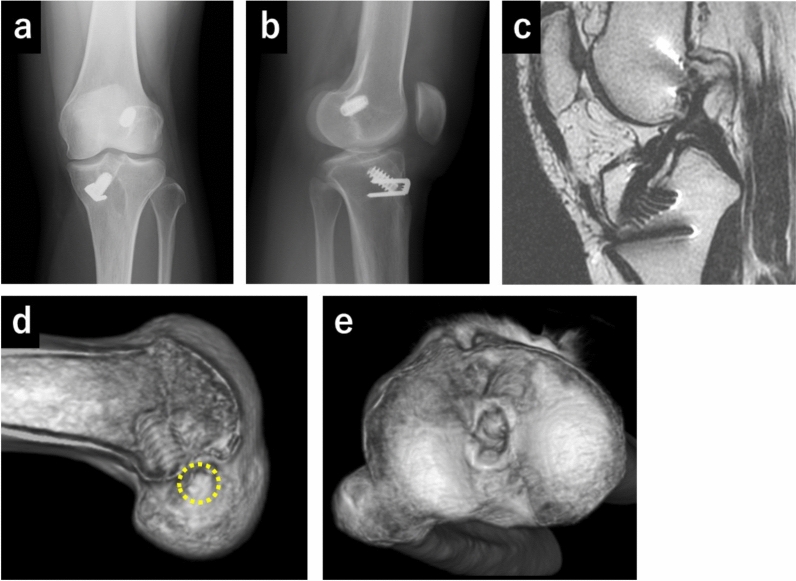

Background: Nonanatomical anterior cruciate ligament (ACL) reconstruction occasionally induces ACL failure without an evident injury episode, necessitating revision surgery. Although the in vivo kinematics of ACL deficiency before primary ACL reconstruction are well documented, the kinematics of ACL failure after nonanatomical reconstruction remain unexplored. The aim of this study is to investigate ACL failure kinematics following nonanatomical reconstruction.

Patients and methods: This study enrolled three patients with ACL failure after nonanatomical reconstruction, 20 normal and 16 ACL-deficient knees. The anteroposterior (AP) translation of the medial and lateral femoral condyles and center of the femur and femoral rotation relative to the tibia during squatting were evaluated using a two- to three-dimensional registration technique under fluoroscopy.

Results: Medial AP translation of the nonanatomically reconstructed knee in one patient showed posterior location and abnormal kinematics compared with the ACL-deficient knees. In contrast, the lateral AP position of the nonanatomically reconstructed knees in two patients were more posteriorly located and showed more abnormal kinematics than the ACL-deficient knees. Central AP translation of the nonanatomically reconstructed knees in two patients was located more posteriorly throughout the range of midflexion. Femoral rotation of the nonanatomically reconstructed knees showed abnormal kinematics compared with that of the normal and ACL-deficient knees.

Conclusions: By independently assessing the medial and lateral aspects of the femur, the medial or lateral condyle of the femur of nonanatomically reconstructed knees exhibited a more pronounced abnormality compared with ACL-deficient knees. The femur of the nonanatomically reconstructed knees showed abnormal rotational kinematics. Considering the kinematic aspect, nonanatomical ACL reconstruction should be avoided.